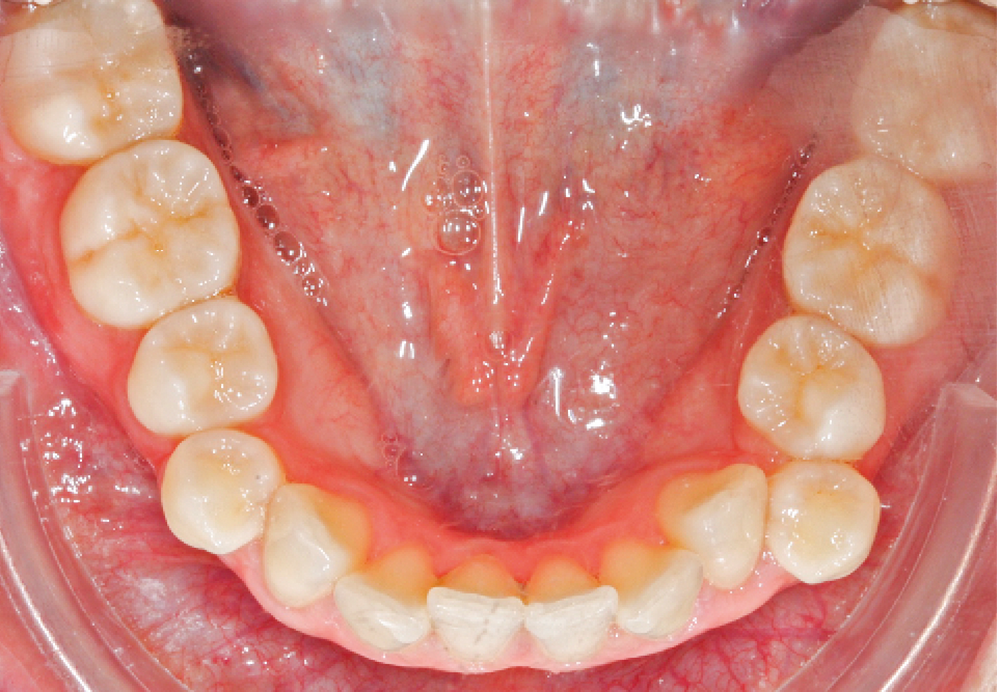

L’examen intra-arcade met en évidence une hygiène bucco-dentaire irréprochable, favorable à un traitement en technique linguale. Le phénotype parodontal est fin dans la région incisivo-canine mandibulaire. L’encombrement est estimé à 8 mm à la mandibule et à 4 mm au maxillaire (fig. 1). Les arcades ont des formes similaires, en U. Les rapports inter-arcades mettent en évidence une classe 1 d’Angle molaire, une classe 2 d’Angle canine et une supraclusion antérieure (recouvrement : 5 mm ; surplomb diminué). Les milieux inter-incisifs sont déviés entre eux avec une origine mixte (= 1,5 mm) (fig. 2).